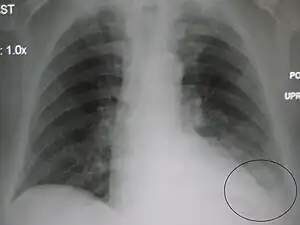

| A chest X-ray showing a very prominent wedge-shape bacterial pneumonia in the right lung | |